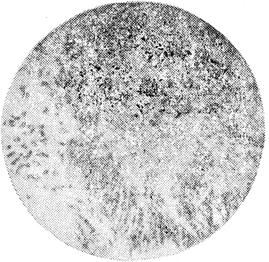

1.用毛细吸管自脓汁或渗出物中吸取黄白色“硫磺样颗粒”(如未见颗粒,可用生理盐水稀释病料,装入烧瓶内并加塞,强力振荡后,倒入平皿,静置使颗粒沉淀于皿底。吸取颗粒样品,置载玻片上,加10~15%氢氧化钾溶液1滴,覆以厚盖玻片,轻压之使颗粒展开,在低倍镜下寻找不规则棍棒形体,再换高倍镜或油镜检查,可见颗粒中央有大量互相交错的丝状体,四周呈棍棒状,末端放射状排列,形似玫瑰花瓣样。如用革兰氏染色法或Kinyoun′s改进的抗酸染色法染色后镜检,则丝状体呈阳性,棍棒形体为阴性。

图18-4 低倍镜下检查、“硫磺颗粒”中的棍形体